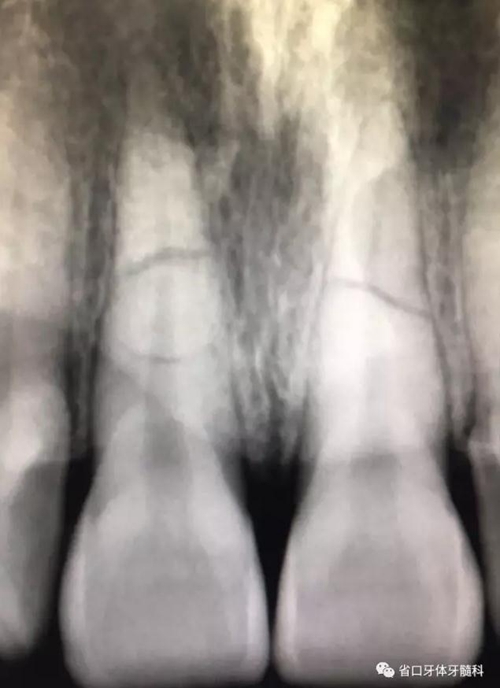

圖2 術前根尖片

X線片:11、21根中段見橫行根折線,無移位,根尖無明顯異常。